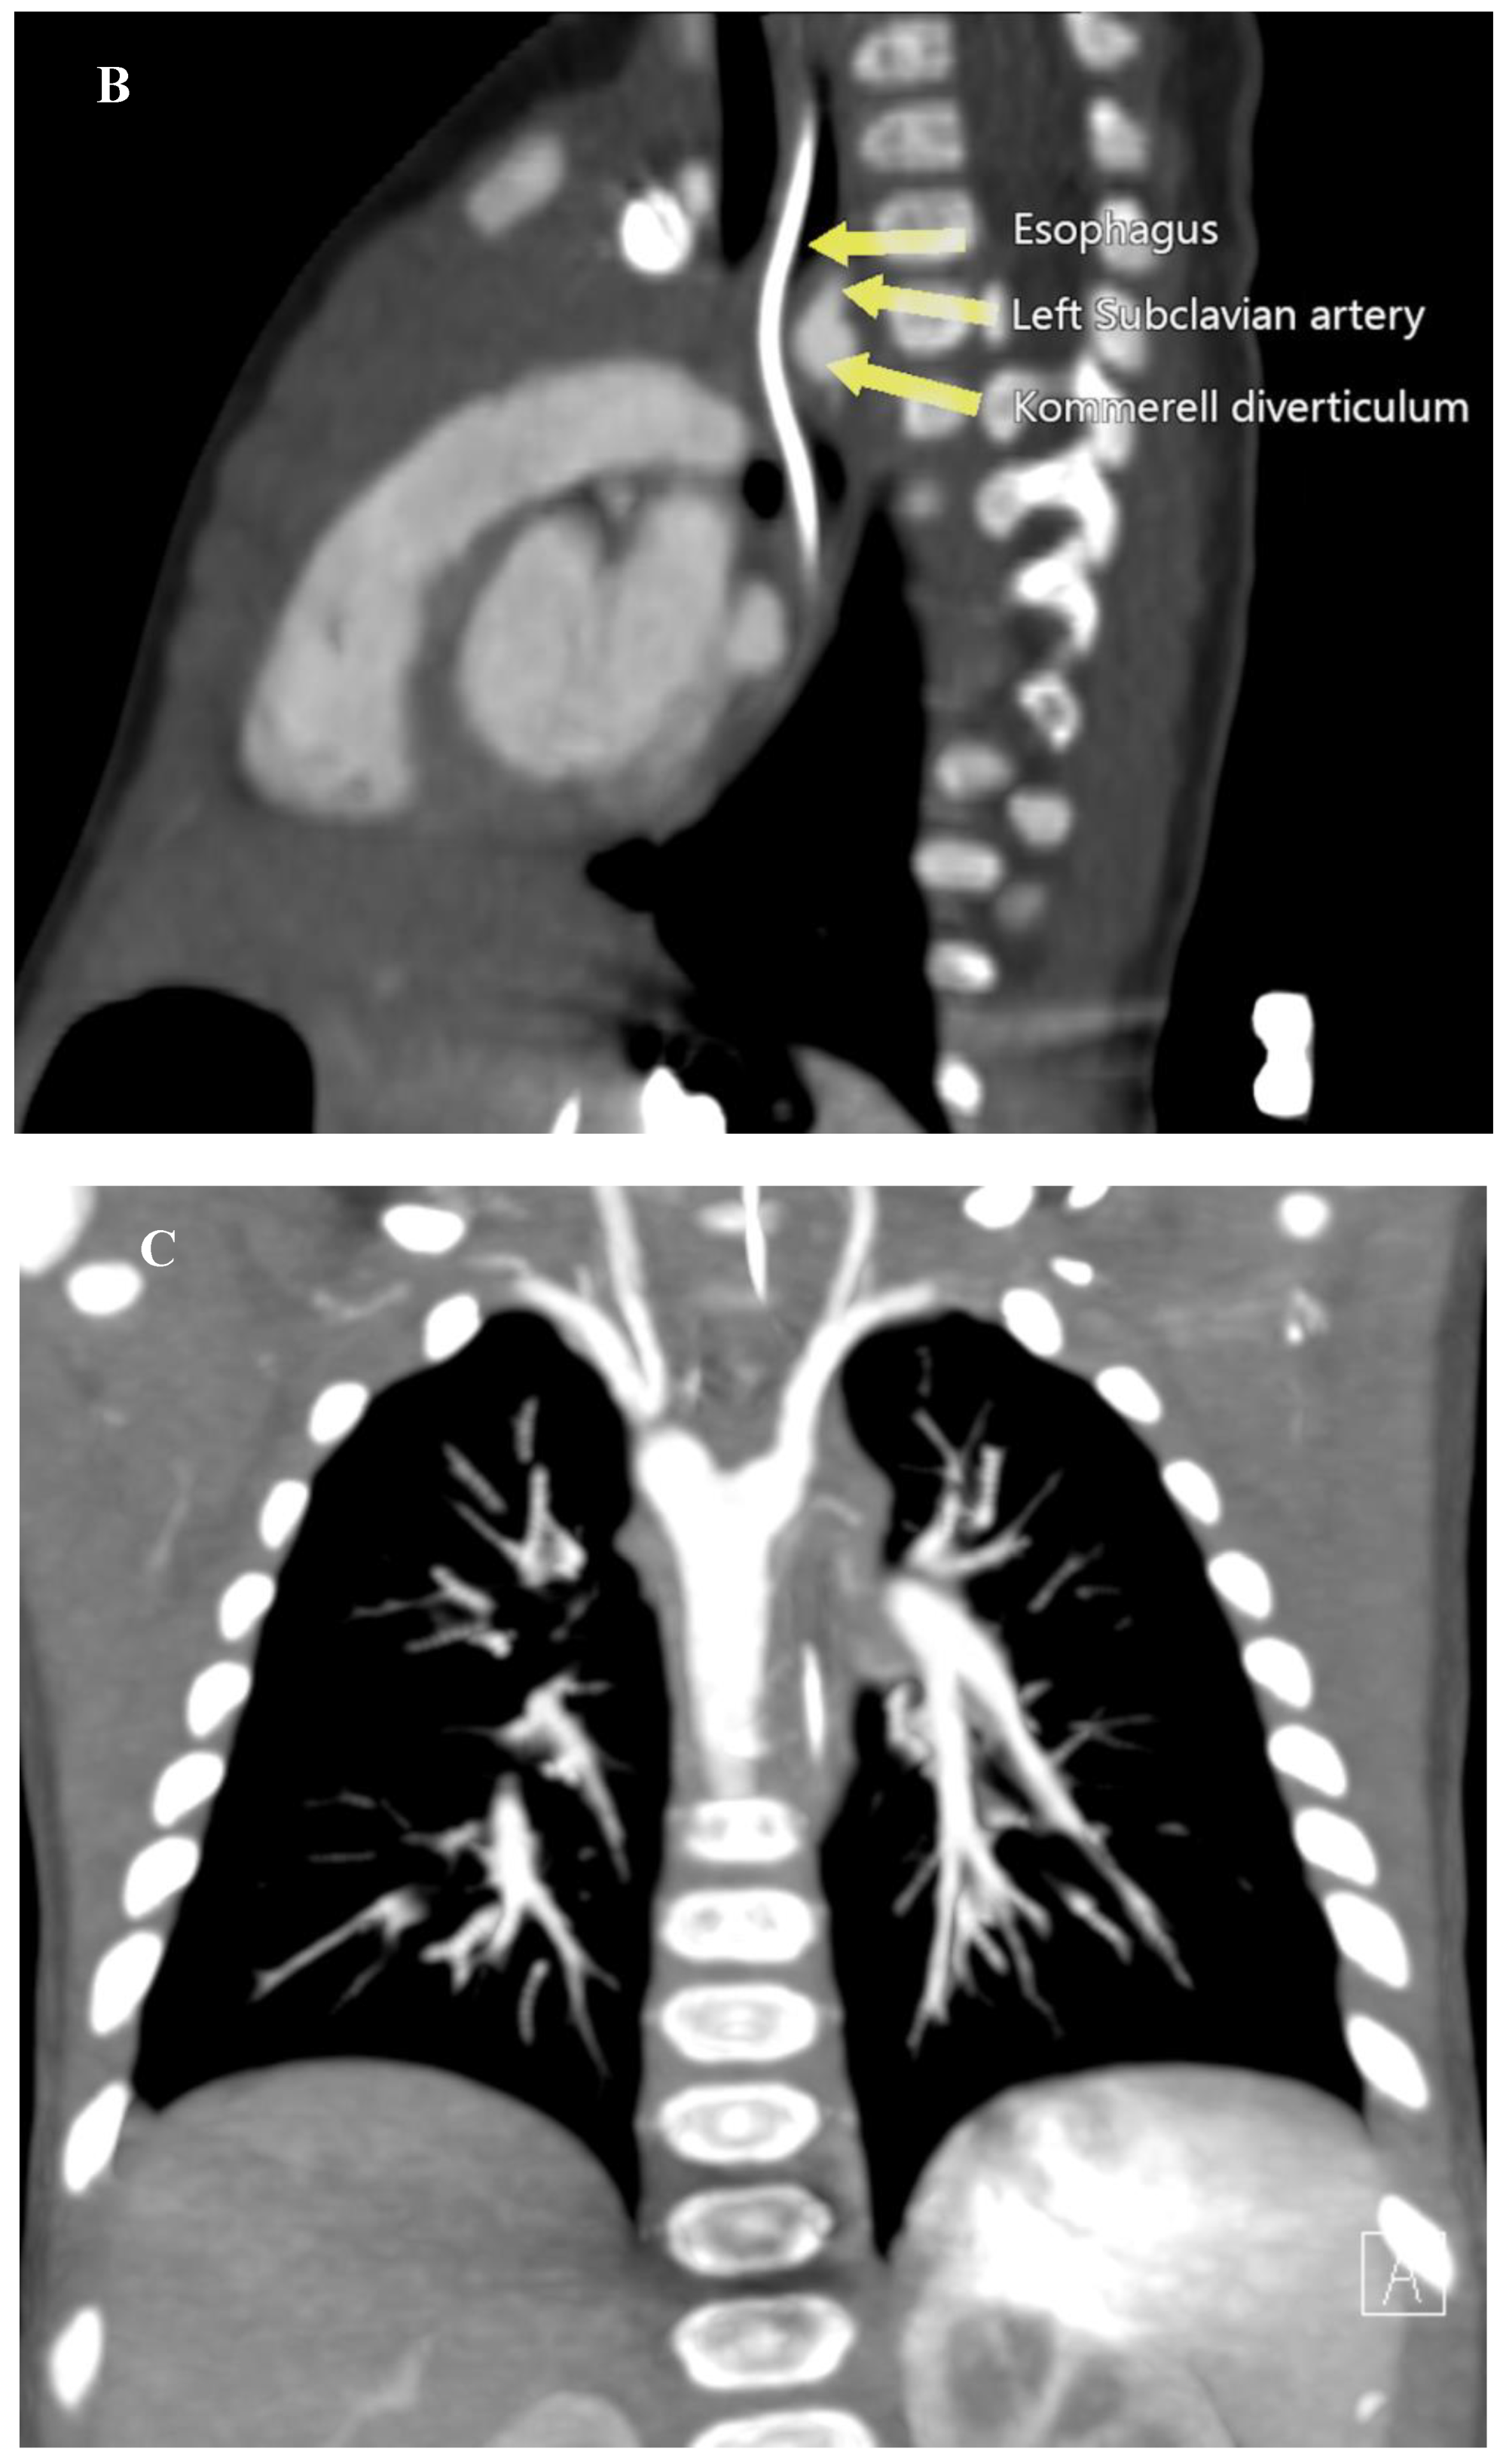

This finding prompted a Computed Tomography Angiography (CTA) which revealed a vascular ring formed by a Right Aortic Arch (RAA), an aberrant Left Subclavian Artery (LSA) originating from an aneurysmal dilation at its base, the so-called Kommerell’s diverticulum (KD), and a Left Ligamentum Arteriosum (LLA) (Figure 2) (Supplementary material 1).

Figure 2. Computed Tomography Angiography. (A) 3D reconstruction of a RAA with the LCA as the first branch, and the retroesophageal aberrant LSA as the fourth branch originating from a KD. (B) sagittal view demonstrating esophageal narrowing and the presence of a nasogastric tube. (C) coronal view showing the aneurysmal dilation of the base of the LSA.